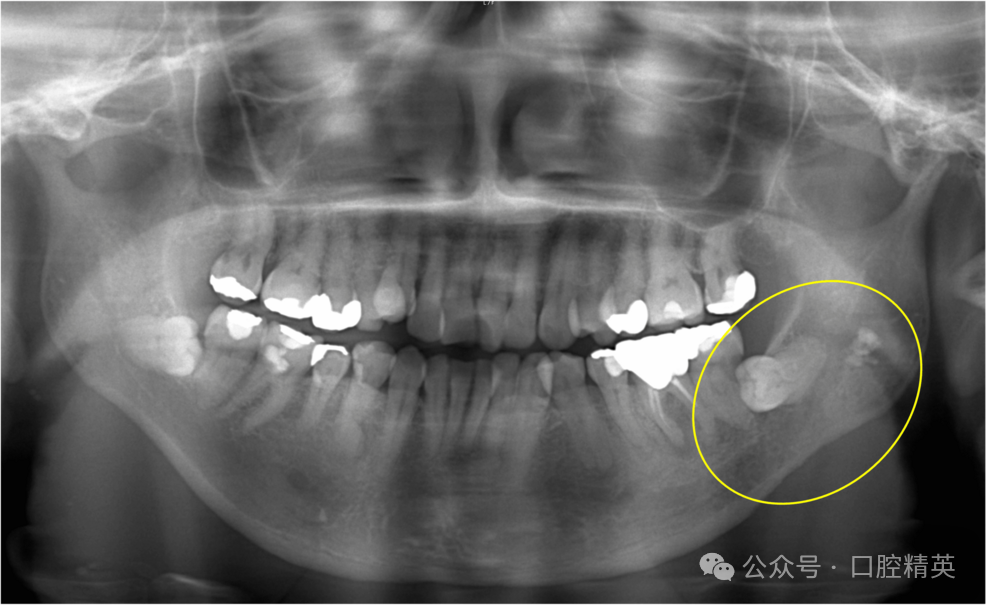

术后曲面体层片显示,38邻近区域及下颌骨下缘骨吸收显著(图4)。

图4 38拔牙后曲面体层片

可见38邻近区域及下颌骨下缘明显骨吸收(黄圈示较术前骨破坏进展,提示非典型下颌骨骨髓炎)。